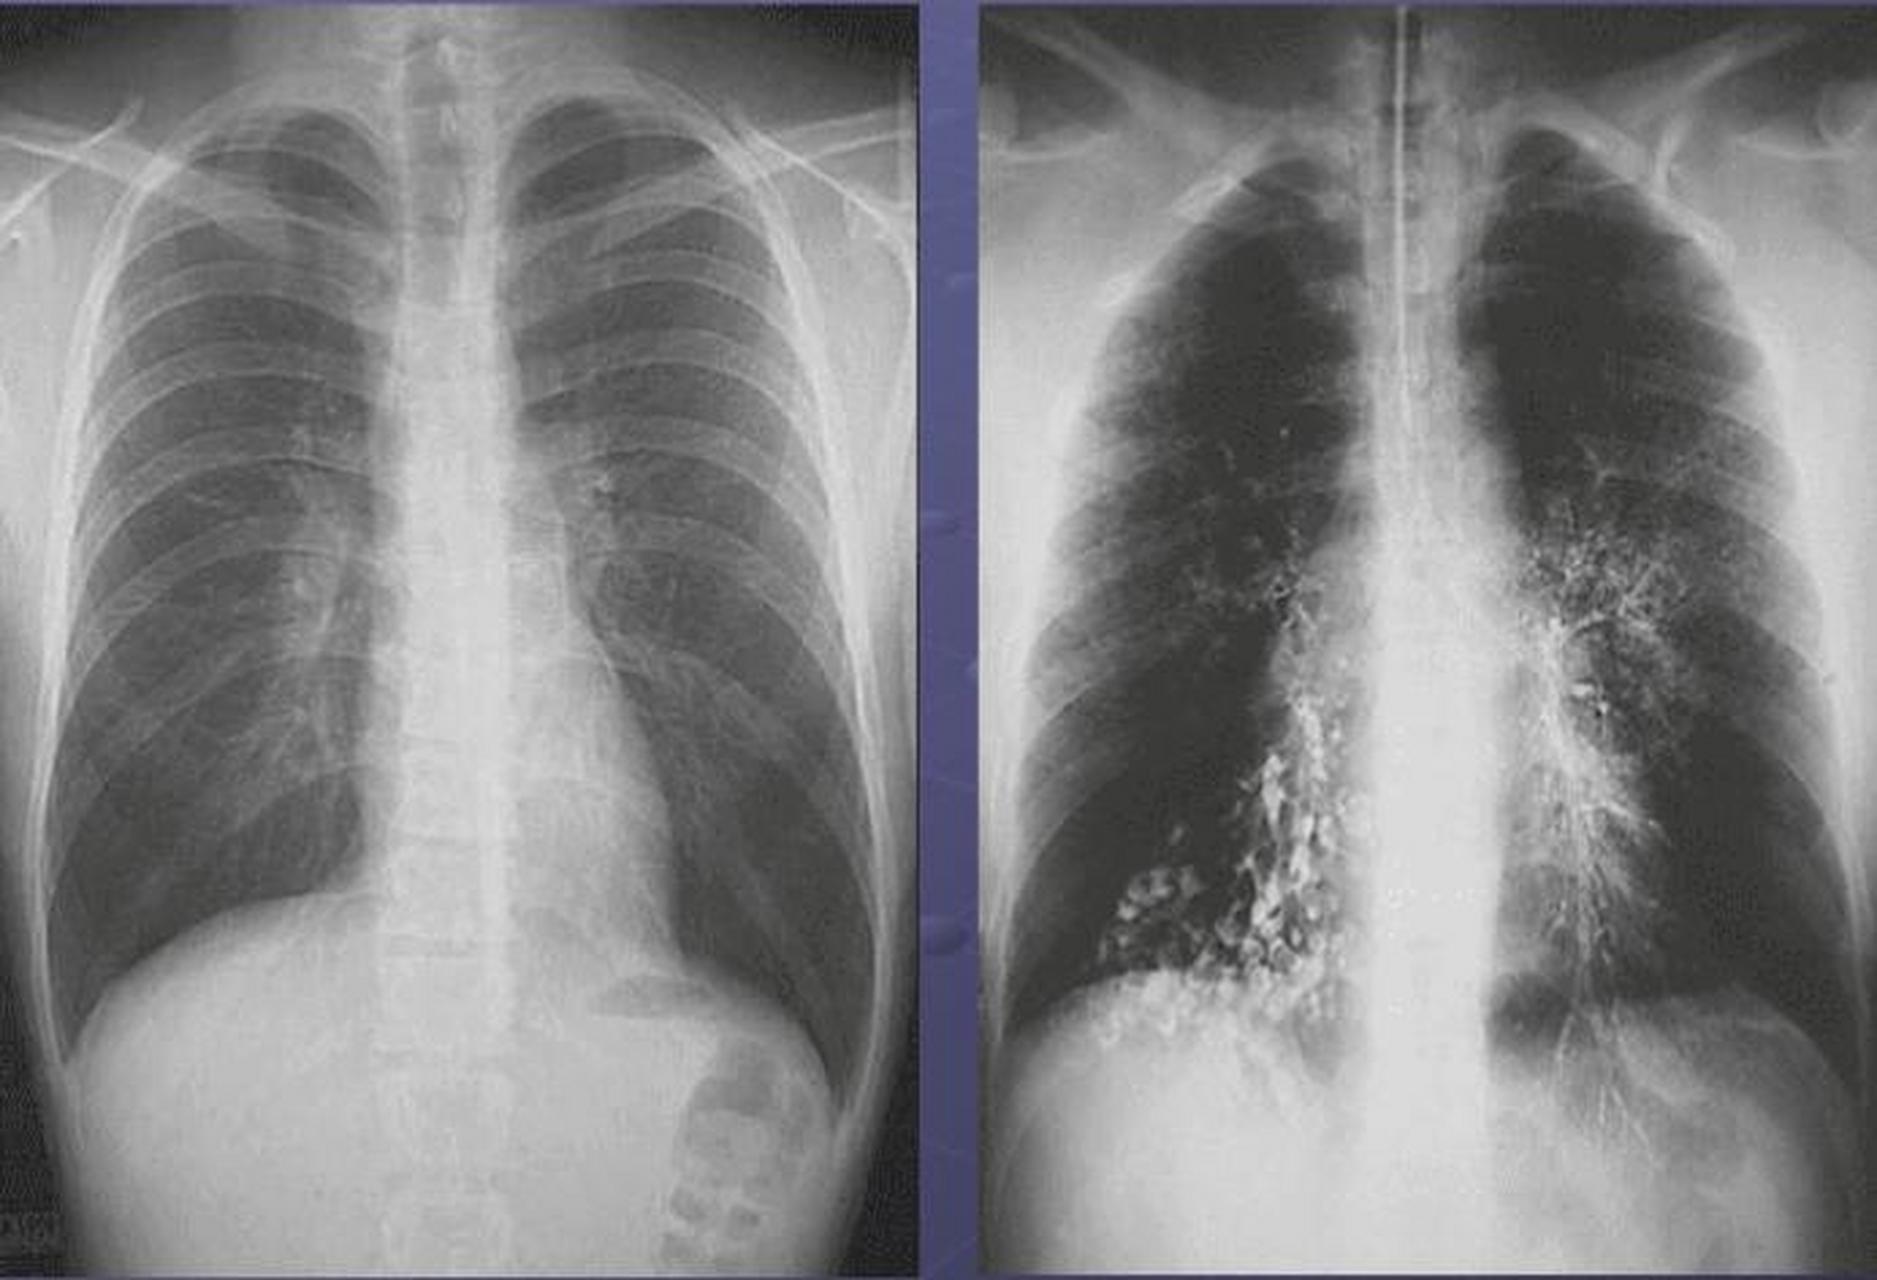

图4-42 支气管扩张x线表现a.胸部正位像;b.侧位像.

囊状支气管扩张x线片下的气道表现为显著的囊腔,呈卷发状或蜂窝样大小